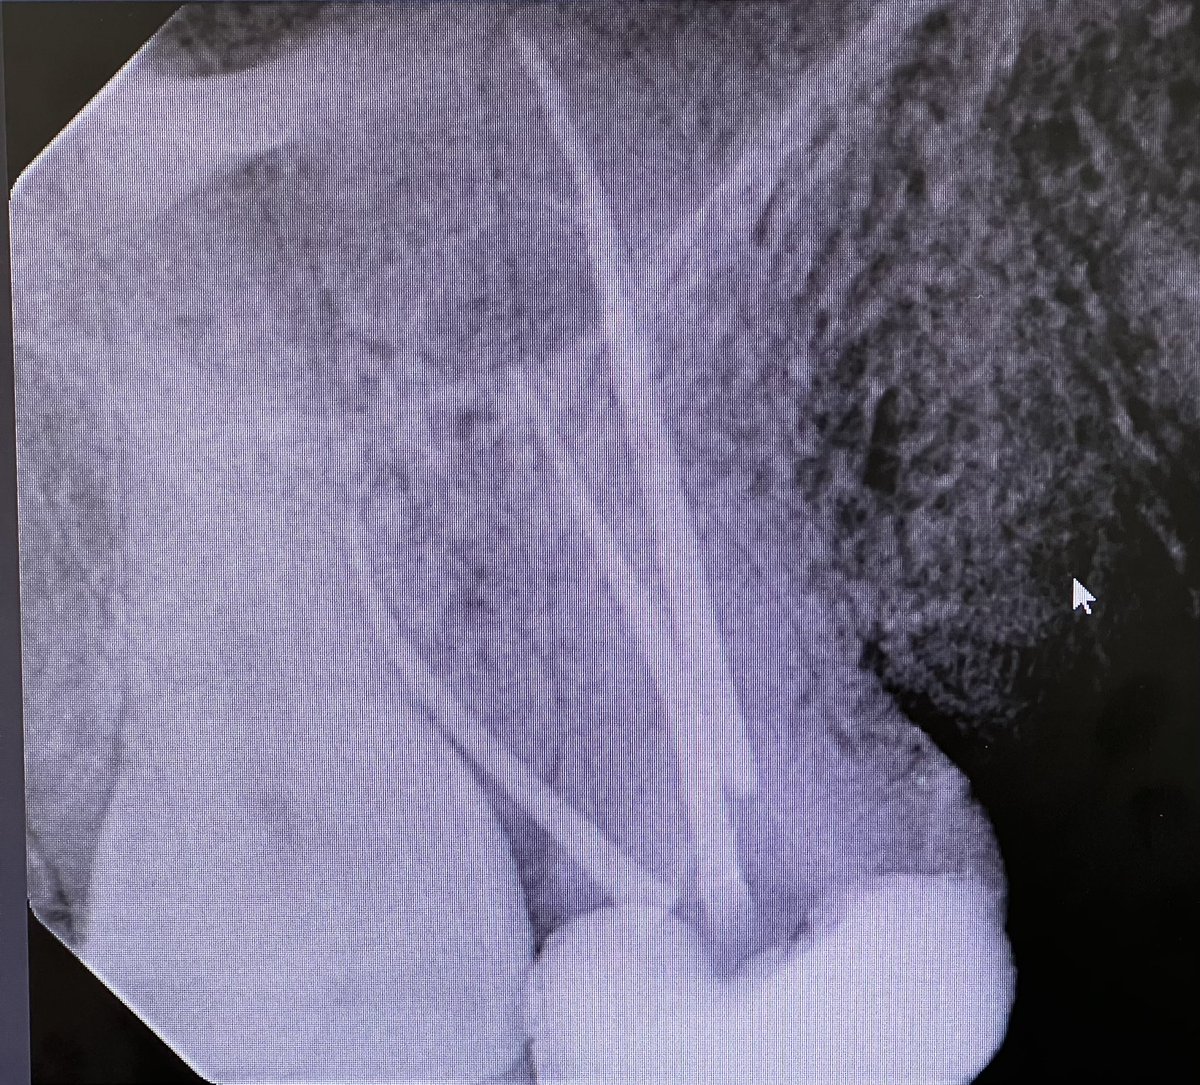

Dx:

24: Symptomatic irreversible Pulpitis w/ SAP

TX:

Non-Surgical RCT (One Visit)